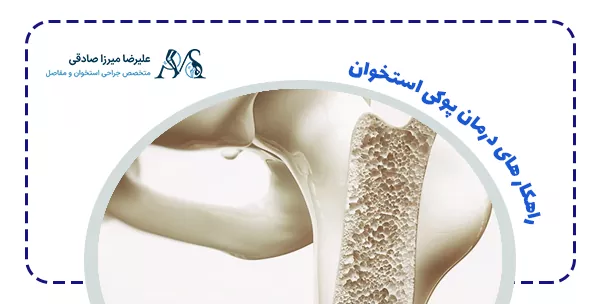

راهکار های درمان پوکی استخوان

درمان این بیماری ترکیبی از دارو، مکمل و تغییر سبک زندگی است. هدف اصلی درمان کاهش سرعت پیشرفت بیماری و پیشگیری از شکستگیها است.

- داروها

داروهای بیسفسفونات رایجترین داروها برای جلوگیری از تخریب بیشتر استخوان هستند. برخی داروهای هورمونی نیز برای زنان یائسه تجویز میشوند. - مکملها

مصرف مکملهای کلسیم و ویتامین D به تقویت استخوانها کمک میکند و از شکستگی جلوگیری میکند. - تغییر سبک زندگی

ورزش، تغذیه مناسب، ترک سیگار و الکل بخشی از درمان محسوب میشود.